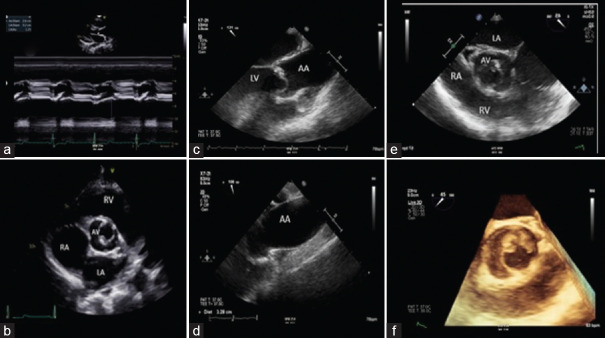

This article provides comprehensive insights into the evaluation of simple congenital heart diseases (CHDs) in adults, emphasizing the pivotal role of echocardiography. By focusing on conditions such as congenital aortic stenosis, aortic coarctation, patent ductus arteriosus, atrial septal defects (ASDs), and ventricular septal defects (VSDs), the review underscores echocardiography's intricate contributions to precise clinical decision-making. Echocardiography serves as the primary imaging modality, offering high-resolution visualization of anatomical anomalies and quantification of hemodynamic parameters. It enables tailored therapeutic strategies through its capacity to discern the dimensions, spatial orientation, and dynamic shunt dynamics of defects such as ASDs and VSDs. Moreover, echocardiography's advanced techniques, such as tissue Doppler imaging and speckle tracking, provide detailed insights into atrial mechanics, diastolic function, and ventricular filling kinetics. Integration of echocardiographic findings into clinical practice empowers clinicians to create personalized interventions based on quantified ventricular function, which spans systolic and diastolic aspects. This approach facilitates risk stratification and therapeutic planning, particularly pertinent in heart failure management within the CHD patient population. In summary, echocardiography transcends its role as an imaging tool, emerging as a precision-guided instrument adept at navigating the complexities of simple CHD in adults. Its ability to expedite diagnosis, quantify hemodynamic impacts, and unravel multifaceted functional dynamics culminates in a comprehensive depiction of these conditions. The fusion of these insights with clinical expertise empowers clinicians to navigate the intricate pathways of CHD, crafting tailored therapeutic strategies characterized by precision and efficacy.